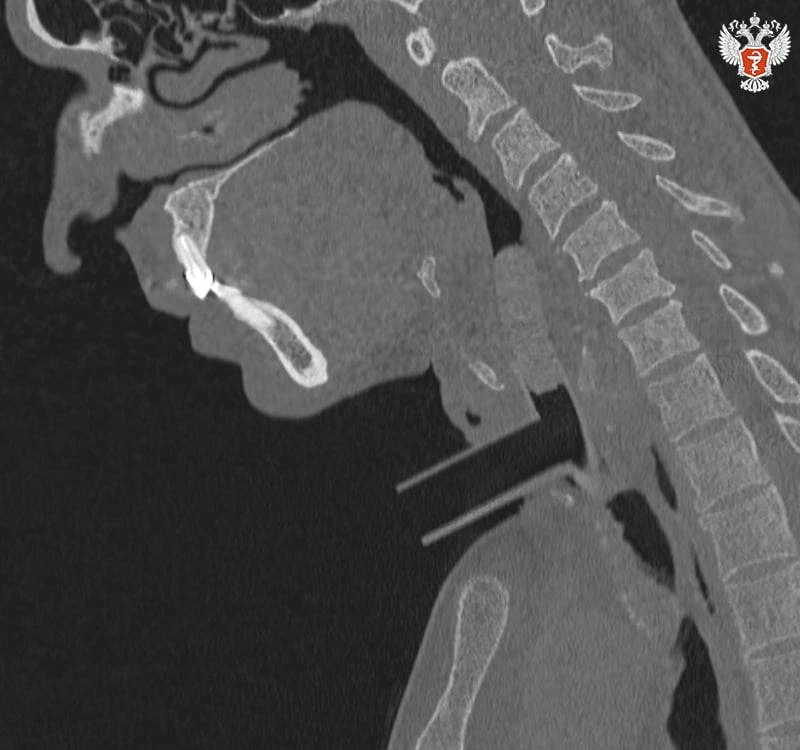

👨‍⚕️ Разработка российских ученых помогла пациентам со стенозом дышать полной грудью

Специалисты Пироговского Университета Минздрава России и НИКИО им. Л.И. Свержевского представили новую систему анатомически адаптированных силиконовых стентов и комплексную тактику лечения хронического рубцового стеноза гортани и трахеи.

💡 Хронический рубцовый стеноз гортани и трахеи — тяжелое заболевание, при котором возникает стойкое сужение просвета дыхательных путей вследствие разрастания плотной соединительной ткани, которое приводит к развитию дыхательной недостаточности.

➡️ Патология может развиться как осложнение после длительной искусственной вентиляции легких, неправильно выполненной трахеостомии, травматических повреждений шеи, химических или термических ожогов. В таких случаях пациенты оставались пожизненно зависимыми от трахеостомической трубки.

Новая методика дает врачам точный инструмент для восстановления дыхания, а пациентам — реальный шанс на полноценную и комфортную жизнь без трубки.

↪️ Ключевые преимущества разработки:

🔴 анатомически адаптированные стенты точно повторяют контуры дыхательных путей, обеспечивая стабильный просвет и минимизируя травму;

🔴 комплексный алгоритм — от 3D-моделирования до контроля заживления — позволяет персонализировать лечение и предсказать результат;

🔴 простота ухода и фиксации дает пациентам возможность самостоятельно обслуживать стент, повышая независимость и качество жизни.

До сих пор лечение таких стенозов было подобно движению по кругу: операция, риск повторного сужения, новая операция. Новая система предлагает управляемый и предсказуемый путь к выздоровлению.